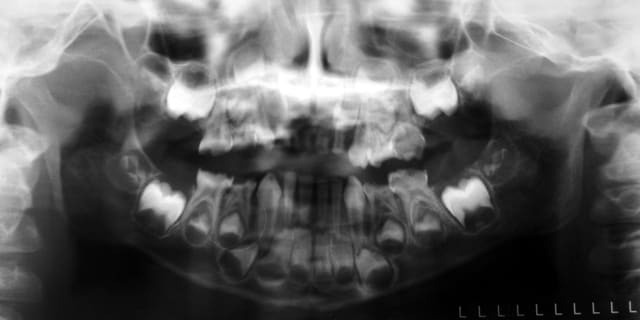

Avulsions multiples à l’hôpital à l'age de 4 ans : il reste uniquement 53/63 en haut et de 83 à 72 en bas.

Aucune prothèses proposés à l'époque. L'enfant mange quand même de tout selon les parents, bien que coupé en petits bouts.

La photo n'est pas très claire : l'enfant propulse et place en permanence son bloc antérieur mandibulaire en avant des canines maxillaires : le bas a egressé vers le haut, le haut vers le bas... Le résultat donne cet encastrement. Magnifique.

Compromis occlusal pour les prothèses, je posterai les photos la semaine prochaine.

Question : 2 bases d'occlusion, montage sur cire, 2 prothèses résines, 13 bambino tooth, 4 crochets adams, 4 fil. Pas de PEI => 489,77 euros de facture prothé, ça vous semble comment ?